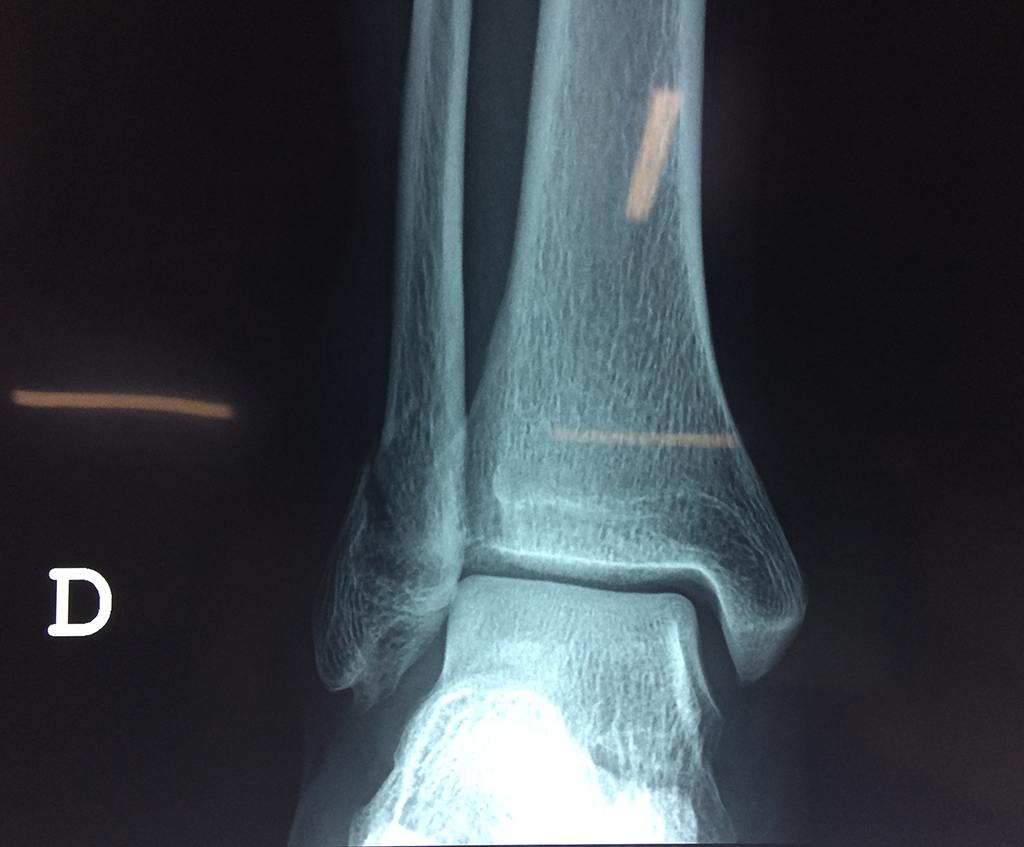

Una fractura de tobillo es la rotura de uno o más de los huesos del tobillo. Estas fracturas pueden ser:

Algunas fracturas de tobillo pueden requerir cirugía si:

- Los extremos de los huesos están desalineados entre sí (desplazados).

Cuando se necesita cirugía, es probable que esta implique el uso de clavijas de metal, tornillos o placas para sostener los huesos en su lugar mientras la fractura se consolida. Los elementos de soporte pueden ser temporales o permanentes.